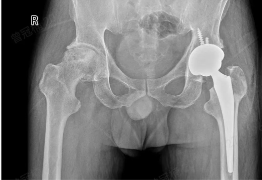

多孔钛金属笼“撑”起坏死股骨头